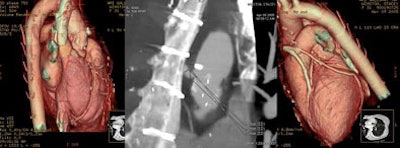

![]() |

| Coronary artery bypass grafts visualized on 64-slice CTA scan. All images courtesy of Dr. David Dowe. |